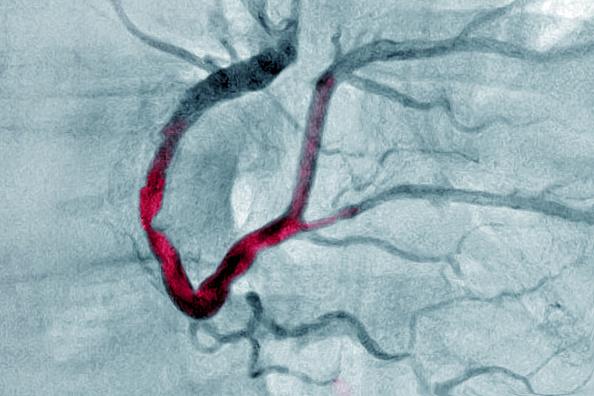

ఇటీవల 18 ఏళ్ల వయసున్న యువకుడు హార్ట్ అటాక్ తో హైదరాబాద్లోని నిమ్స్ ఆసుపత్రికి వచ్చాడు.

పల్మనరీ యాంజీయోగ్రామ్ చేస్తే త్రాంబస్ (రక్తనాళంలో రక్తం గడ్డ కట్టుకోవడం) ఉన్నట్లు తేలింది. అంత చిన్న వయసులో స్టంట్ వేయాలంటే బాధగా అనిపించిందని వైద్యులు చెప్పారు.

ఇదే విషయంపై డాక్టర్ రమాకుమారి మాట్లాడుతూ డయాబెటిస్, బీపీ, హైపర్ టెన్షన్ ఫెయిల్యూర్ను ఇంకా ఎక్కువ చేస్తాయి. ఎకో, ఈసీజీ, కార్డియాక్ ఎంఆర్ఐ, పల్మనరీ యాంజియోగ్రామ్ చేయించుకోవాలి. ఇవన్నీ చేయించుకున్నాకే జిమ్ వంటి వాటికి వెళ్లడం మేలు’’ అని చెప్పారు.